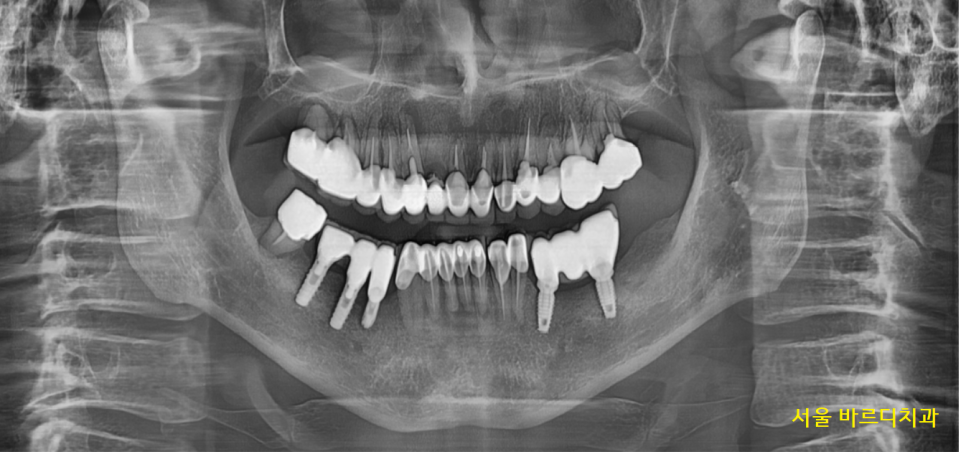

입냄새의 원인은 다양하지만

환자분의 경우 잇몸에서 염증이 나오고 있었는데요.

23.06.07